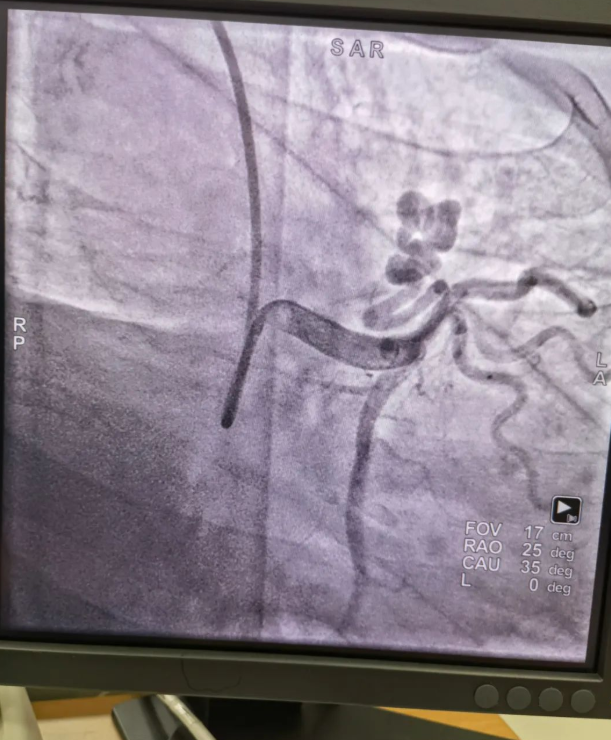

不久前,來自新疆的患者石先生去年至今反復(fù)胸悶、氣短、胸痛,就診于新疆某院,懷疑“冠心病”,住院行冠狀動脈造影術(shù),石先生造影提示“冠狀動脈肺動脈瘺”,而他并非“冠心病”,所以給予的“冠心病”治療,效果不佳。出院后仍反復(fù)出現(xiàn)胸痛、胸悶、氣短等癥狀,經(jīng)親友介紹了解到西安國際醫(yī)學(xué)中心醫(yī)院心臟病醫(yī)院心臟內(nèi)科二病區(qū)曾廣偉主任,多年來潛心研究心臟病介入治療,成功主刀救治了許許多多高危復(fù)雜病例,尤其是在先心病及結(jié)構(gòu)性心臟病封堵,以及冠心病、心律失常射頻消融及起搏治療等方面積累了豐富的診療經(jīng)驗。

此病例罕見,在曾廣偉從醫(yī)18年生涯里曾碰到有2個印象深刻的病例,患者分別是53歲和66歲,當時建議患者入院進行動脈瘺的封堵術(shù),但患者和家屬考慮到這個手術(shù)案例極少,風(fēng)險也高,均未接受手術(shù)治療建議,只是能采取藥物保守治療,出院后隨訪得知患者癥狀緩解效果不佳,后來在隨訪中也與53歲患者失去了聯(lián)系,而66歲患者因冠狀動脈肺動脈瘺出現(xiàn)反復(fù)心衰,在當?shù)蒯t(yī)院藥物治療,短短2年時間,患者因為動脈瘺未及時手術(shù)失去了生命。所以此次患者石先生到訪,曾廣偉主任在詳細掌握病例資料基礎(chǔ)上,果斷建議進行動脈瘺的封堵術(shù)治療,為了提高手術(shù)成功率和精準度,曾廣偉主任搜集相關(guān)診療資料,反復(fù)推演論證,經(jīng)過相當充足的準備工作,于5月18日成功進行了封堵手術(shù),完全堵上了瘺口。

患者術(shù)后第2天,已經(jīng)沒有明顯的胸悶、氣短、胸痛等癥狀,目前身體狀態(tài)良好。本次手術(shù)曾廣偉主任及其團隊,采取從右手臂一根血管進入,并在2小時之內(nèi)完美封堵,創(chuàng)口小,痛苦小。手術(shù)雖然難度大、風(fēng)險高,相關(guān)案例也少,但是曾廣偉主任主刀即在巔峰,這樣一臺完美的手術(shù)靠的不是運氣,是豐富的臨床手術(shù)經(jīng)驗,扎實的專業(yè)知識儲備,以及對醫(yī)療事業(yè)的孜孜追求。

冠狀動脈瘺是指冠狀動脈與心腔、冠狀靜脈、肺動脈等的異常連接,是一種少見的先天性心臟病,發(fā)病率為1.3%。而冠狀動脈肺動脈瘺是冠狀動脈與肺動脈之間產(chǎn)生的一種血管性瘺口,導(dǎo)致冠狀動脈里的血液流入肺動脈里,使冠狀動脈里血液流量減少,出現(xiàn)心肌供血不足,冠狀動脈肺動脈瘺會使患者出現(xiàn)胸部疼痛、胸悶、呼吸困難、頭暈、乏力等一系列癥狀,隨著疾病不斷進展,可引發(fā)心功能的障礙和心肌缺血,肺動脈會逐漸形成肺動脈高壓,還可能導(dǎo)致動脈瘤的破裂,甚至威脅病人的生命安全,所以早期發(fā)現(xiàn)和治療冠狀動脈肺動脈瘺,對病人的預(yù)后改善具有重要的意義。